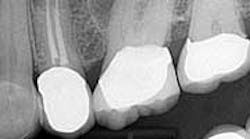

Case report A healthy 61-year-old female presents with a chief complaint of pain and discomfort in the upper left quadrant. A radiograph revealed a large radiolucency at the apex of tooth No. 12. An irregular root apex was also noted. Clinically No. 12 was sensitive to percussion and palpation in the buccal vestibular area. There was no response to cold. Diagnosis was necrotic tooth No. 12 with associated periapical abscess. RCT was recommended and the patient was referred to a specialist for completion. RCT was completed — no complications were noted and the prognosis was given as good. (Figs. 1 and 2) The patient was placed on recall by the endodontist for reevaluation of the lesion in 12 months.Fig 1. Fig. 2Eight months later, the patient presented back to the office stating that she felt pressure again in the upper left area. A radiograph of No. 12 showed an increased radiolucency around the apex of tooth No. 12. Furthermore, there was a draining fistula in the buccal vestibule. Diagnosis was persistent infection/disease, likely due to the initial presentation and presence of the cyst. (Fig. 3)